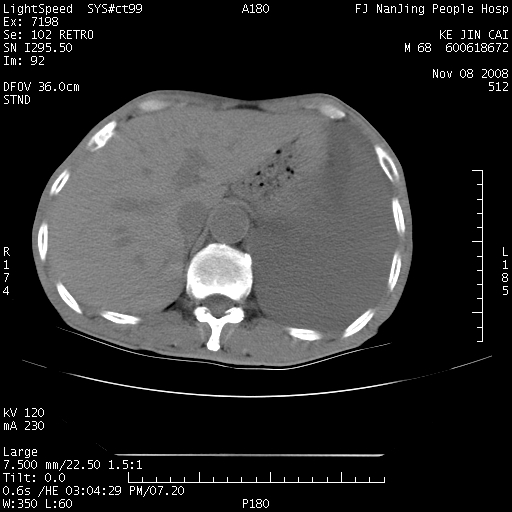

是个很有看头的病例,咋人气那么不旺?没多少人兴趣呢?这个病例几大怪:1   恶性肿瘤侵犯心肌左房怪,心肌一般不会被恶性肿瘤侵犯吧?2   左下肺均匀实变怪,内无含气,有别一般不张实变,含气肺泡完全为液体取代,而非一般不张实变的肺萎陷,冷不丁还以为是肿大的脾脏3   肿瘤本身怪,像tb肺不张4   这么有看头的病例没人气怪。呵呵。

左肺恶性肿瘤侵犯肺动脉,左心房内瘤栓,胸膜转移。